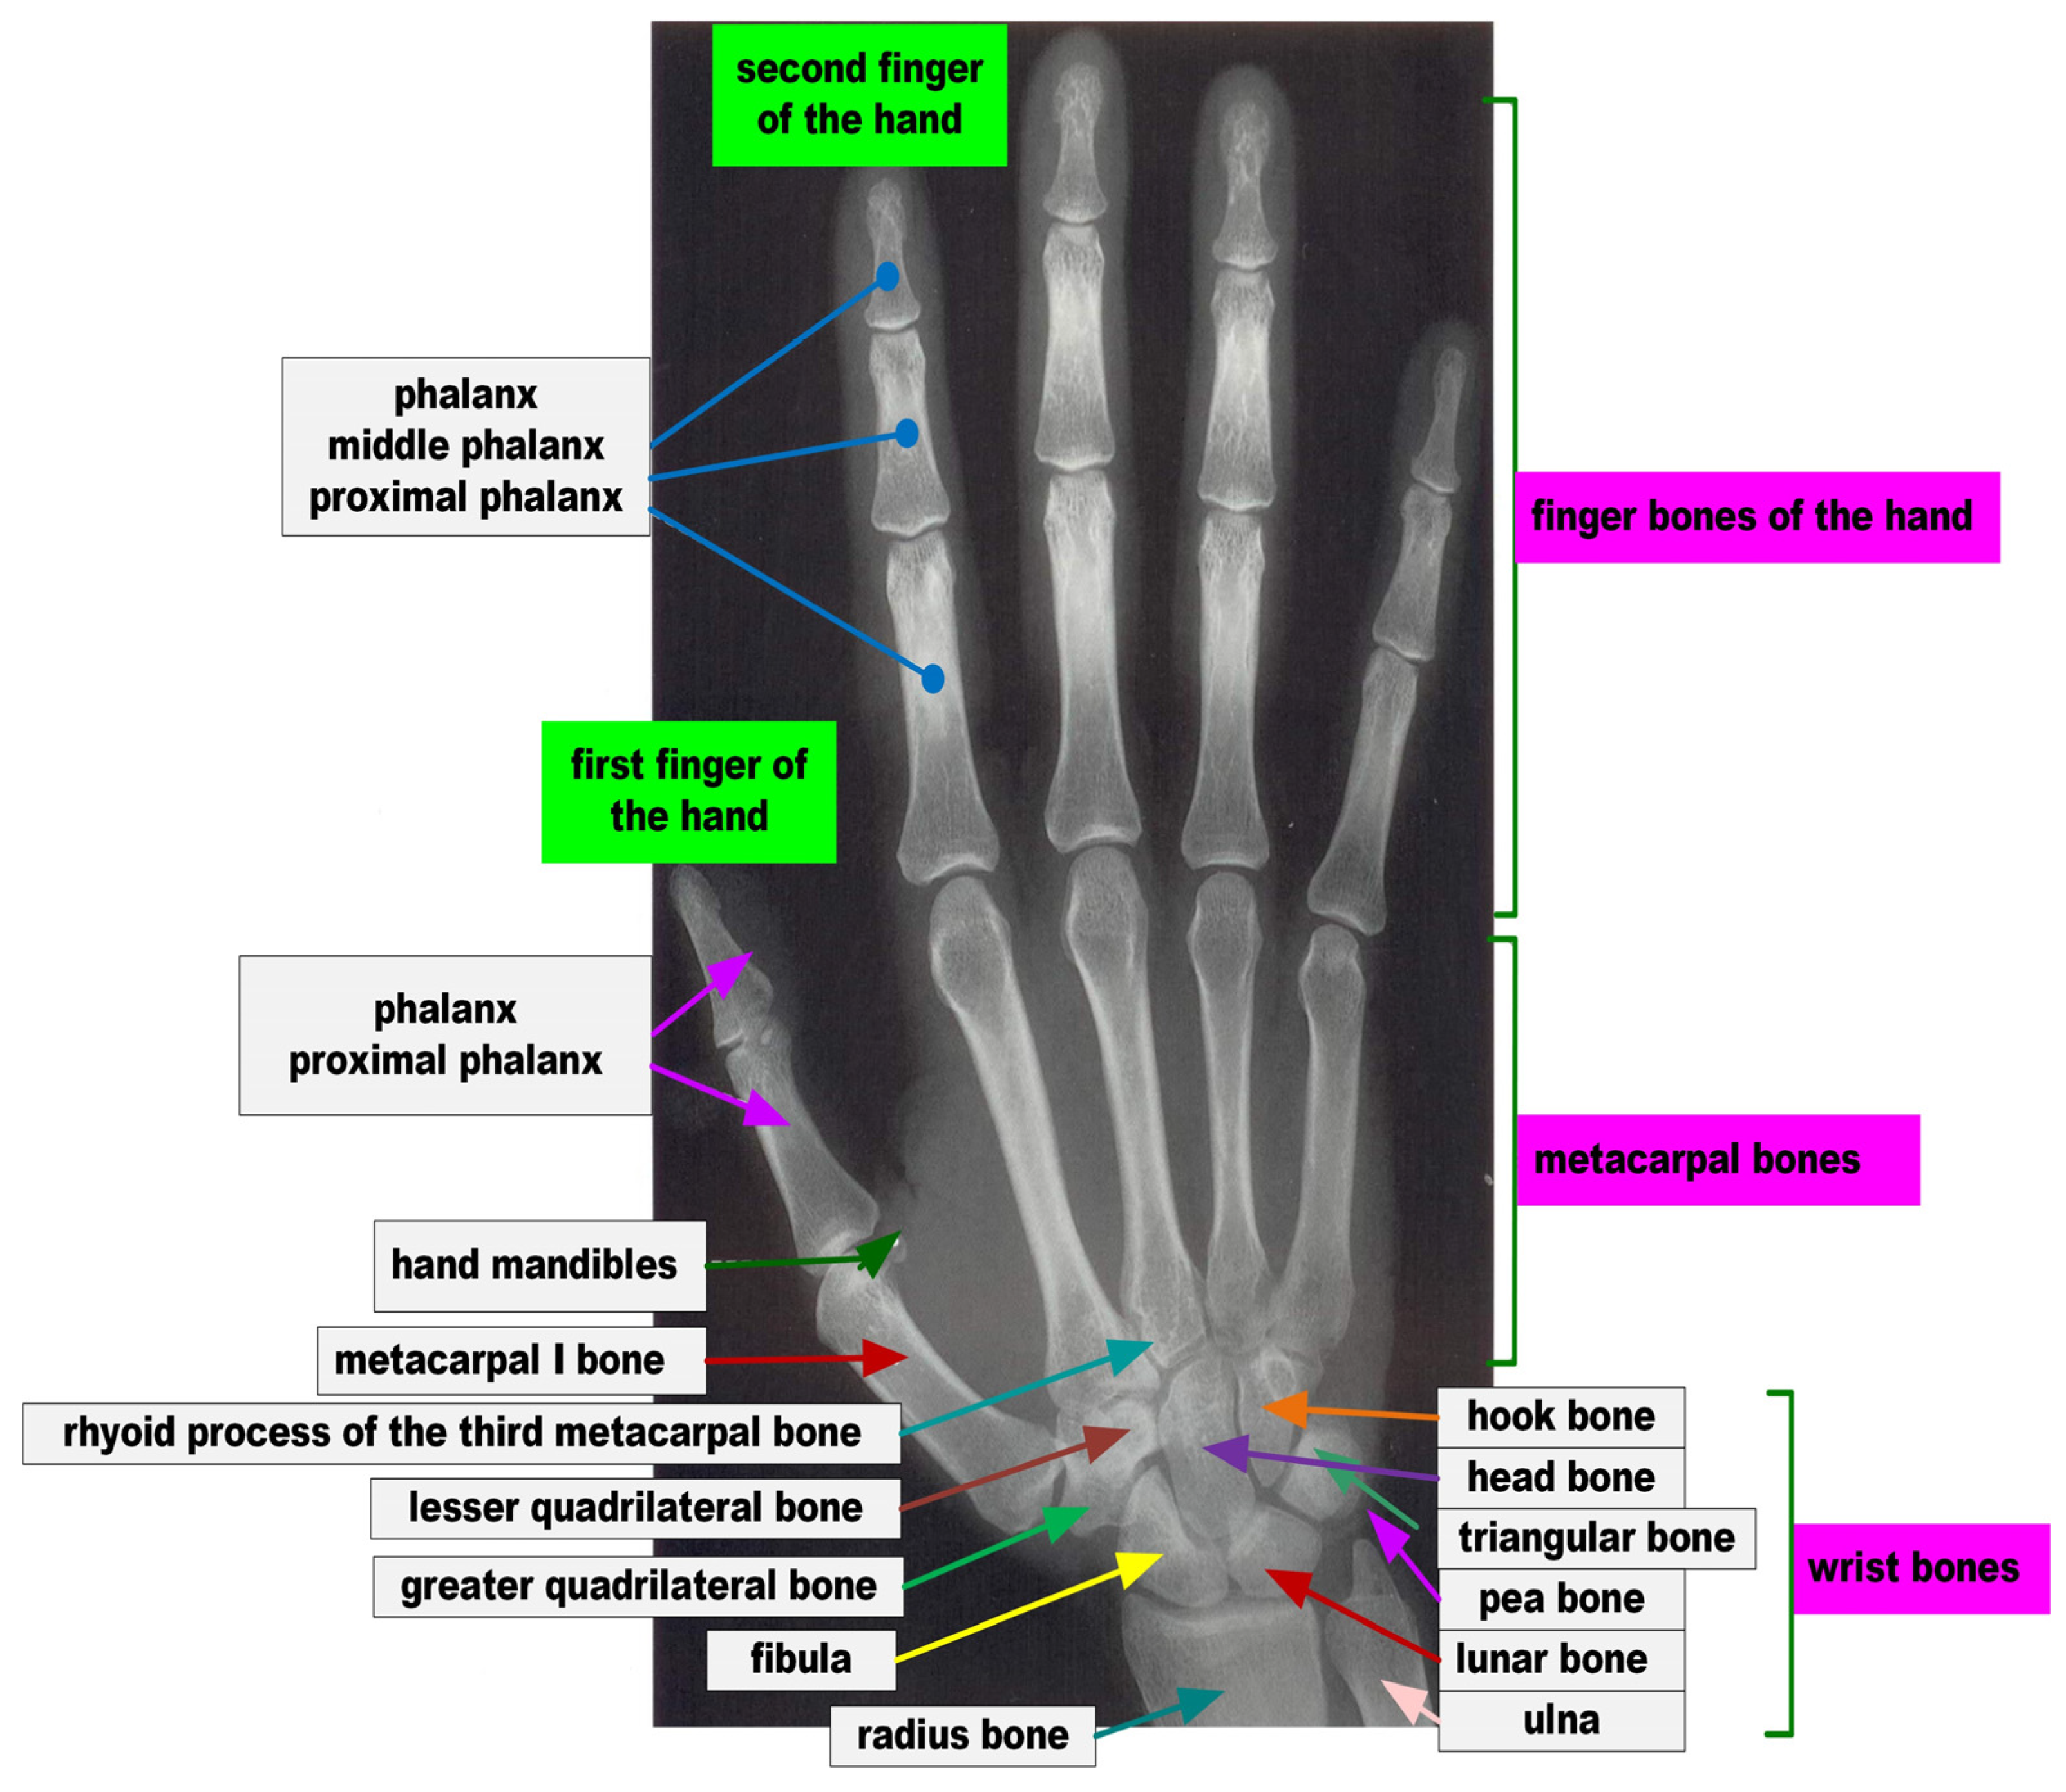

The correct image of the bones of the hand is shown in Figure 5, in which the bones of the palm of the right hand were imaged, divided into the bones of the fingers, metacarpals, and wrist.

Figure 5.

The bones of the palm of the right hand, divided into the bones of the fingers, metacarpus, and wrist. Source: own development.